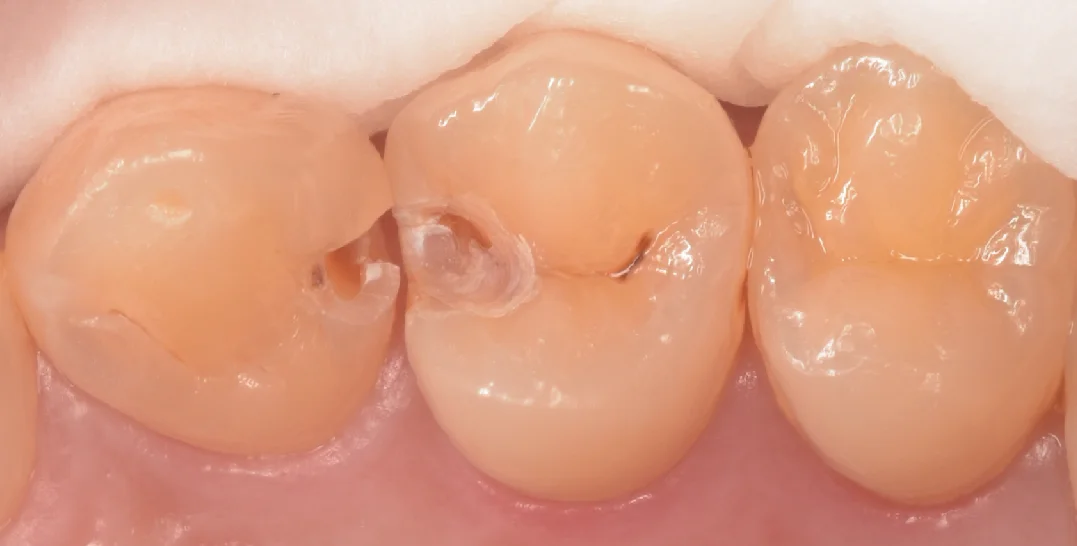

まずは術前からです。

画像上で左二つの治療を今回行いました。

真ん中は古いプラスチックが欠けていますがぱっと見はむし歯はなさそうに見えます。

対して左側の歯はどう見ても内部で大きくなってそうな、黒っぽいのが透けて見えている状態です。

軽く削ってみたのがこちらの写真です。

中央の歯のプラスチックはまだ取り切れてはいないですが、すでに虫歯が露出していますね。

左側の歯は表面のエナメル質がほぼ消失して、大きな穴が空いていたのがわかります。